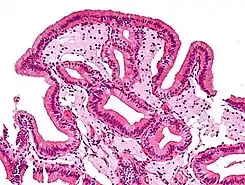

Células espumosas en colesterolosis de la vesícula biliar.

Las células espumosas aparecen en la pared de vasos sanguíneos formando una veta de grasa. Este es el inicio de la formación de la placa de ateromas y son derivadas de macrófagos y células musculares lisas de la pared arterial. En casos de hiperlipidemia crónica, las lipoproteínas conglomeradas dentro de la íntima de los vasos sanguíneos se oxidan por la acción de los radicales libres generados ya sea por los macrófagos, células endoteliales o, especialmente en placas avanzadas, también de células musculares lisas.[1] Los macrófagos digieren las lipoproteínas de baja densidad (LDL) oxidadas por un proceso llamado endocitosis, dirigidos por receptores scavenger, que son distintos de los receptores de LDL. La LDL oxidada se acumula en los macrófagos y otros fagocitos, que luego son conocidas como células espumosas.[2] Estas forman estrías de grasa en las placas de ateroma de la túnica íntima de las arterias.